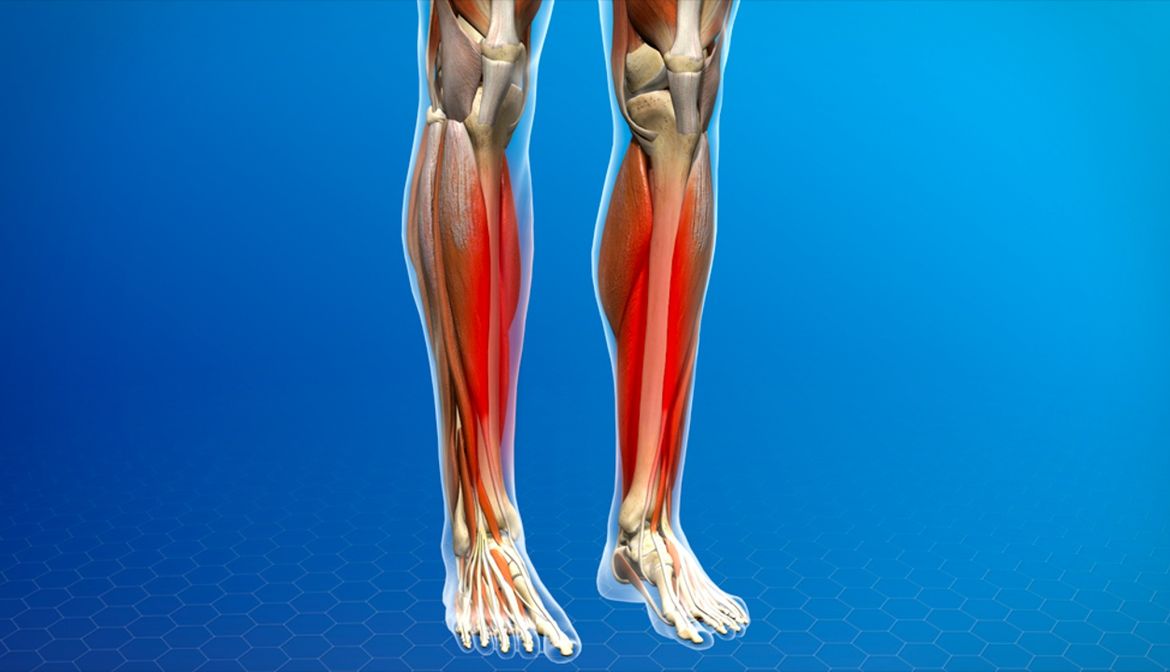

Tibial Stress Syndrome Sore Legs ? There’s nothing worse than achy, throbbing shins, maybe after an intense Irish Dance training session. If you’re experiencing pain along your shins in one